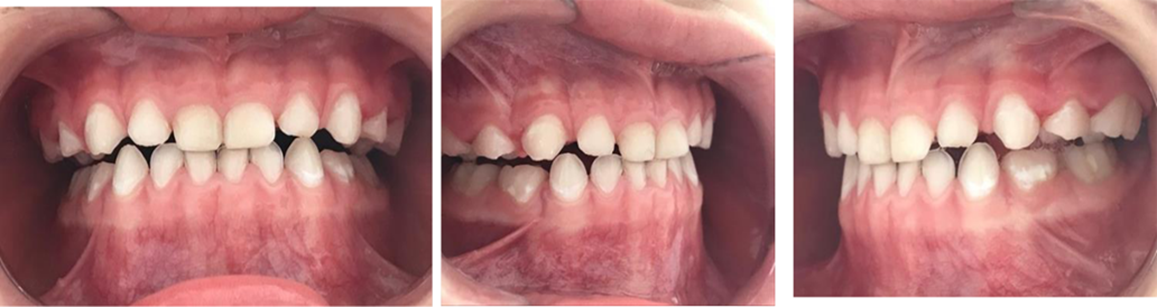

Figura 3. Fotos intrabucales. Vista lateral.

Figura 9. Fotos intrabucales postratamiento. Vista frontal y perfil.